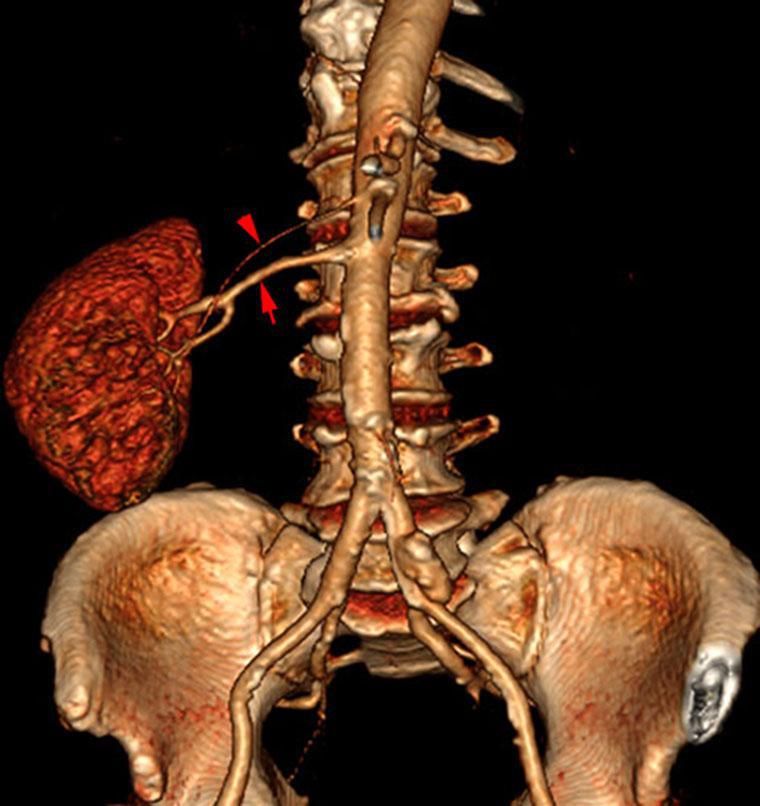

Hipoplasia renal 2